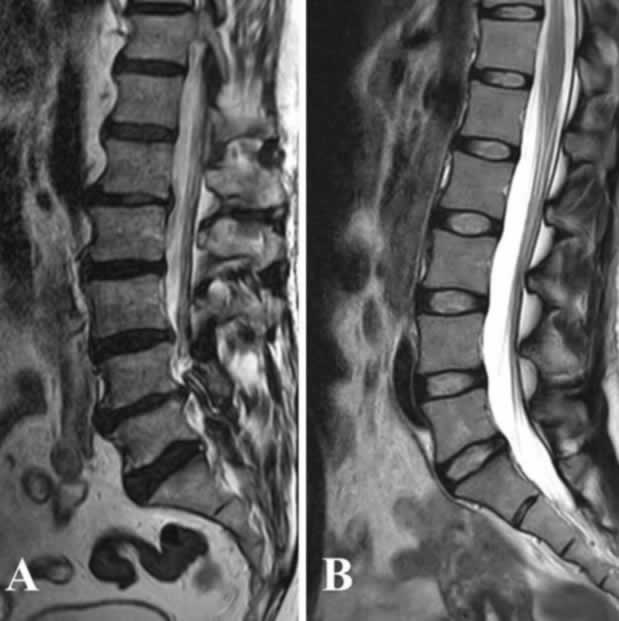

Для оценки дегенерации межпозвонкового диска используются сагиттальные МРТ-изображения поясничного отдела позвоночника в Т2 режиме.

A. Дегенерации межпозвонковых дисков по Pfirrmann: в основном неоднородные черные диски без каких-либо разделений между ядром и фиброзным кольцом; спадение (коллапс) дисков на уровнях L1-L2 и L4-L5 позвонков.

B. Поясничные межпозвонковые диски с высокой эластичностью при низкой степени дегенерации по Pfirrmann; видна однородная структура дисков с ярким гиперинтенсивным сигналом и нормальной высотой.